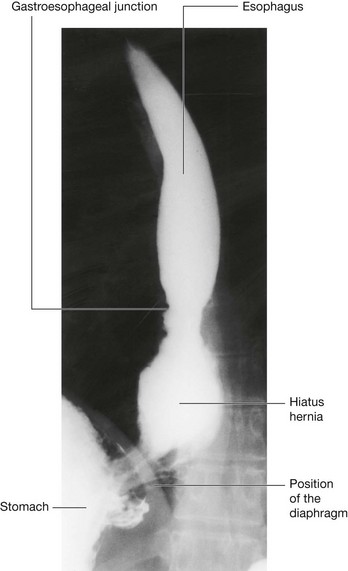

Hiatus hernia

At the level of the esophageal hiatus, the diaphragm may be lax, allowing the fundus of the stomach to herniate into the posterior mediastinum (Fig. 4.134). This typically causes symptoms of acid reflux. Ulceration may occur and may produce bleeding and anemia. The diagnosis is usually made by barium studies or endoscopy. Treatment in the first instance is by medical management, although surgery may be necessary.

Fig. 4.134 Lower esophagus and upper stomach showing a hiatus hernia. Radiograph using barium.